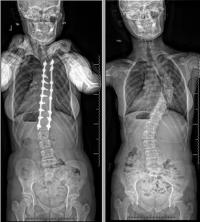

Zoe started to work with John from East Coast in the Columbia Orthopedics office to be put in braces for her spine. "John was amazing with Zoe and all the braces he made for her,” said mom. This brace monitoring went on for a few years along with Schroth therapy, until the brace was becoming unbearable. Since surgery was more dangerous because of Zoe's genetic condition, especially when it came to anesthesiology, Dr. Vitale took this into consideration and told the Schimmels that the best option would be to have the surgery immediately since he would not need to fuse Zoe's spine all the way, which meant less time under anesthesia.

Post-surgery, so many things have been better for Zoe; her back in general looks better she had a big hump before and it’s not there anymore, she is walking more balanced, and breathing better. She also sees a pulmonologist regularly and has had “crackle sounds” in her lungs since she was in preschool, and at her last appointment there were no “crackles” in her lungs. Zoe has also grown taller, and her development has progressed.